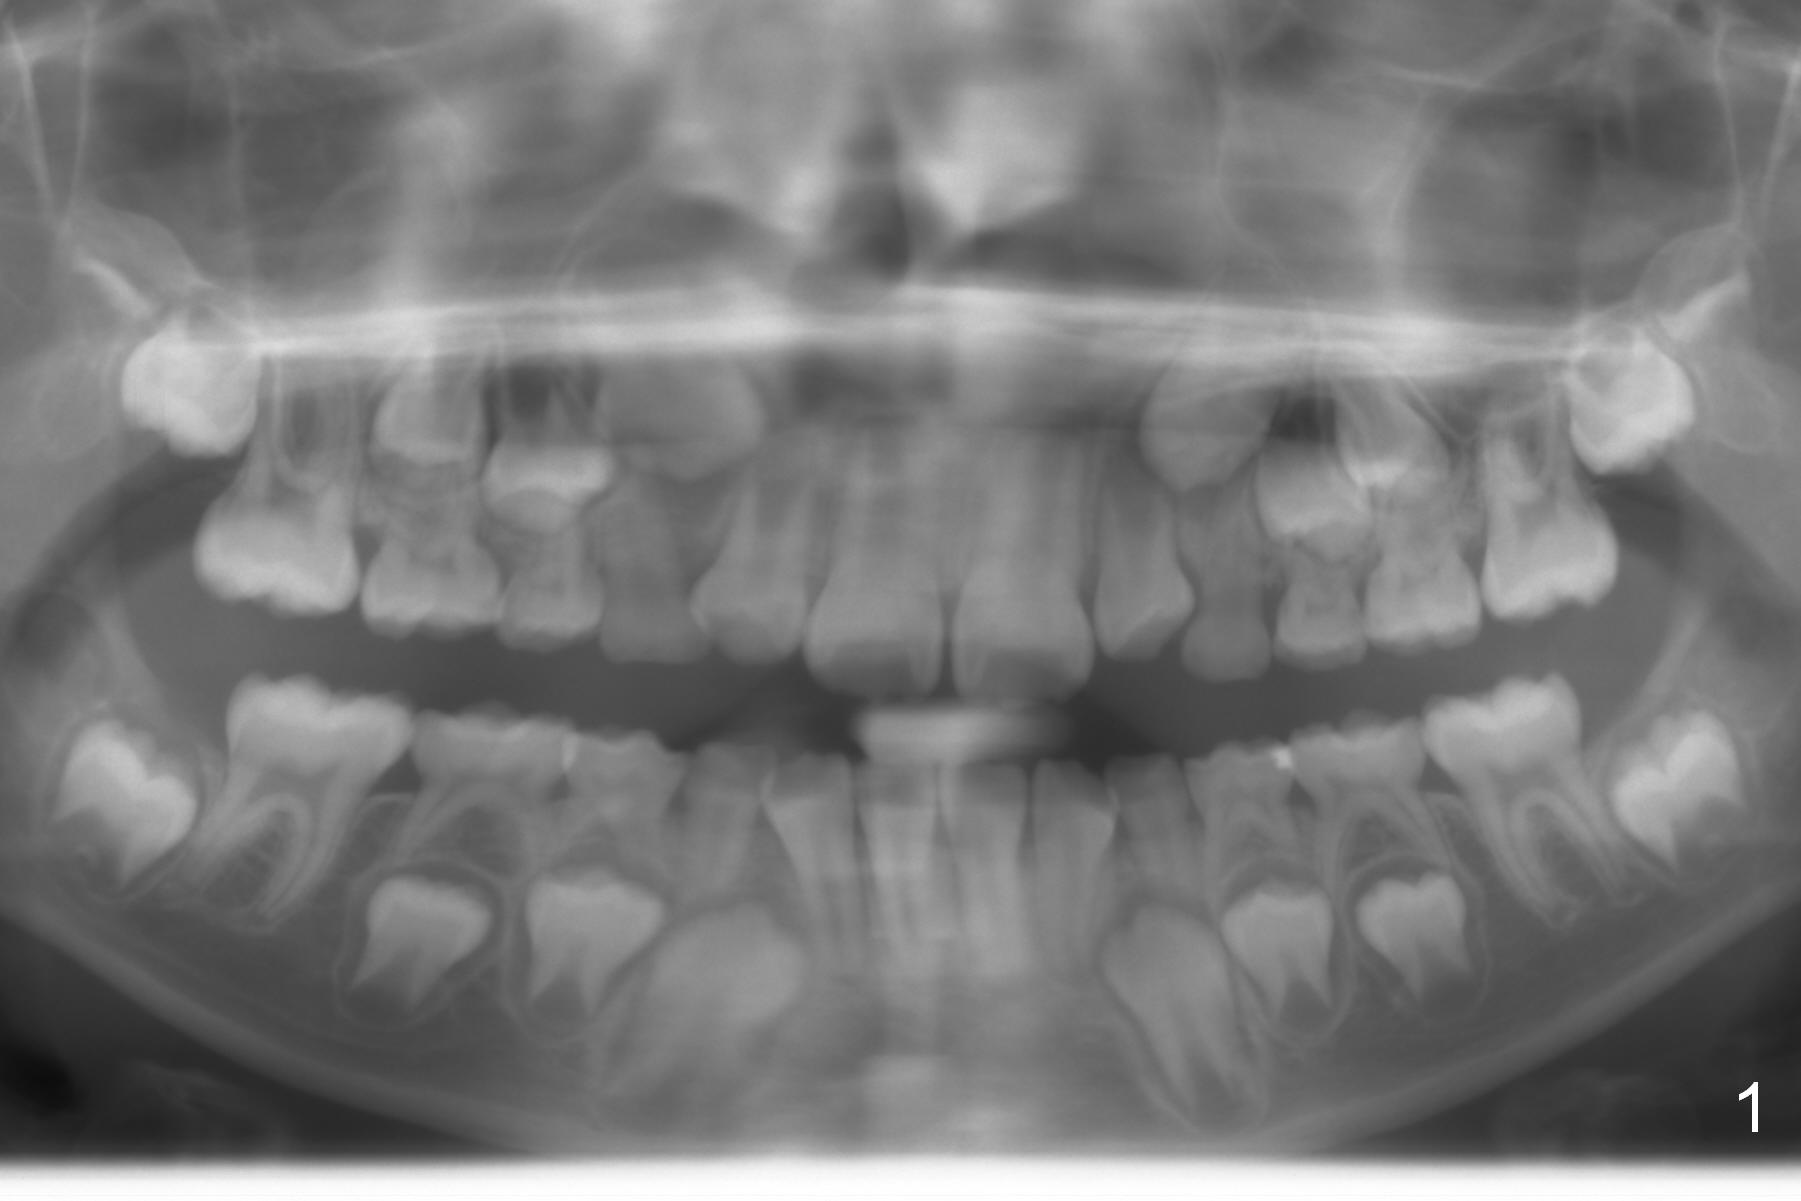

A 11-year-old boy has history of asthma. His father has sleep apnea with similar Class II malocclusion. Pan was taken for the boy 3 years ago (Fig.1). His mother wants to have orthodontic treatment as early as possible, because of protrusive upper anterior teeth. The dentition is permanent except the upper left canine and 1st molar (Fig.7,10,12,13 C, D). It appears that there is bilateral Class II occlusion at canine by half a tooth (Fig.9-12). The malocclusion and facial profile can be easily corrected with extraction of the upper 1st bicuspids.

On the other hand, orthodontics without extraction may improve the mandibular position by using Class II retraction. The tongue may be advanced with increased pharyngeal space. Sleep apnea possibility may be reduced. What is your choice of treatment?